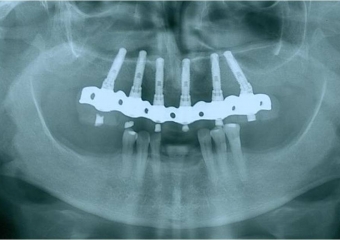

Raio X final

Raio X de controle, realizado em Junho de 2013